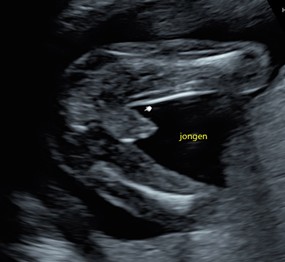

Week 16

De ogen van je baby kunnen vanaf nu licht en donker waarnemen, door de gesloten oogleden heen. Je kindje gaat steeds meer en krachtiger bewegen. Het is vroeg, maar sommige moeders voelen de eerste bewegingen al in deze periode van hun zwangerschap. Ook is het nu beter mogelijk het geslacht te zien via een echo. Dit is nog wel afhankelijk van de beeldkwaliteit (dit kan wisselen per apparaat, maar ook per vrouw, bijvoorbeeld bij overgewicht) en ook moet je kindje er een beetje goed voor gaan liggen.

13 cm

120 g